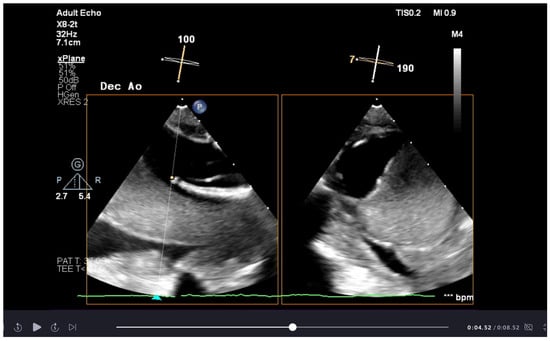

After the elephant trunk deployment, the rapid stabilisation and exclusion of the false lumen due to thrombosis and occlusion in the first 24–48 h after the operation (see Figure 1) causes a progressive reduction in the spinal cord blood supply that can lead to delayed paraplegia [56,57,58]. As part of the postoperative adaption to this event, the damaged collateral network undergoes intensive angiogenesis within 24–48 h after the operation and ischaemic areas are revascularised [59]. There is early experience in spinal cord preconditioning through minimally invasive segmental artery coil embolisation, attempting to develop neo-vessels and improve spinal resilience before the operation [60,61]. Ultimately, the perioperative goal is to bridge to vascular recovery and maximise the flow in the existing vascular bed, ensuring a high perfusion pressure after surgery [56,61].

Bilateral radial artery pressure monitoring is helpful during SACP and after subclavian reimplantation to ensure adequate flow as part of the spinal cord protection. Femoral artery pressure monitoring detects the blood flow in the descending aorta, although the prosthesis deployment needs to be confirmed with transoesophageal echocardiography (Videos S1 and S2). Transoesophageal echocardiography (TOE) is essential in the preoperative period in assessing the severity of the aortic pathology and for surgical planning, mainly when there is aortic root involvement. If a guidewire is used to direct the deployment of the elephant trunk prosthesis, TOE helps identify that the guidewire is in the true lumen. Once the prosthesis is deployed and the flow in the descending aorta is restored, TOE is used to confirm the correct deployment of the graft and assess the flow dynamic between the true and false lumen (Video S3) [73].

The following supporting information can be downloaded at: https://www.mdpi.com/article/10.3390/jcdd12040130/s1, Video S1: Transoesophageal echocardiogram showing thrombosis of the false lumen post deployment of aortic graft. Video S2: Transoesophageal echocardiogram showing aortic dissection of the descending lumen with blood flow through true lumen. Video S3: Transoesophageal echocardiogram showing blood flow the deployed graft.

Figure 1. Transoesophageal echocardiogram image of thrombosis of false lumen post deployment of aortic graft.